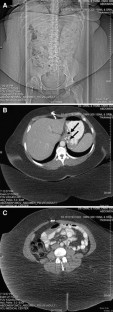

Fig. 2